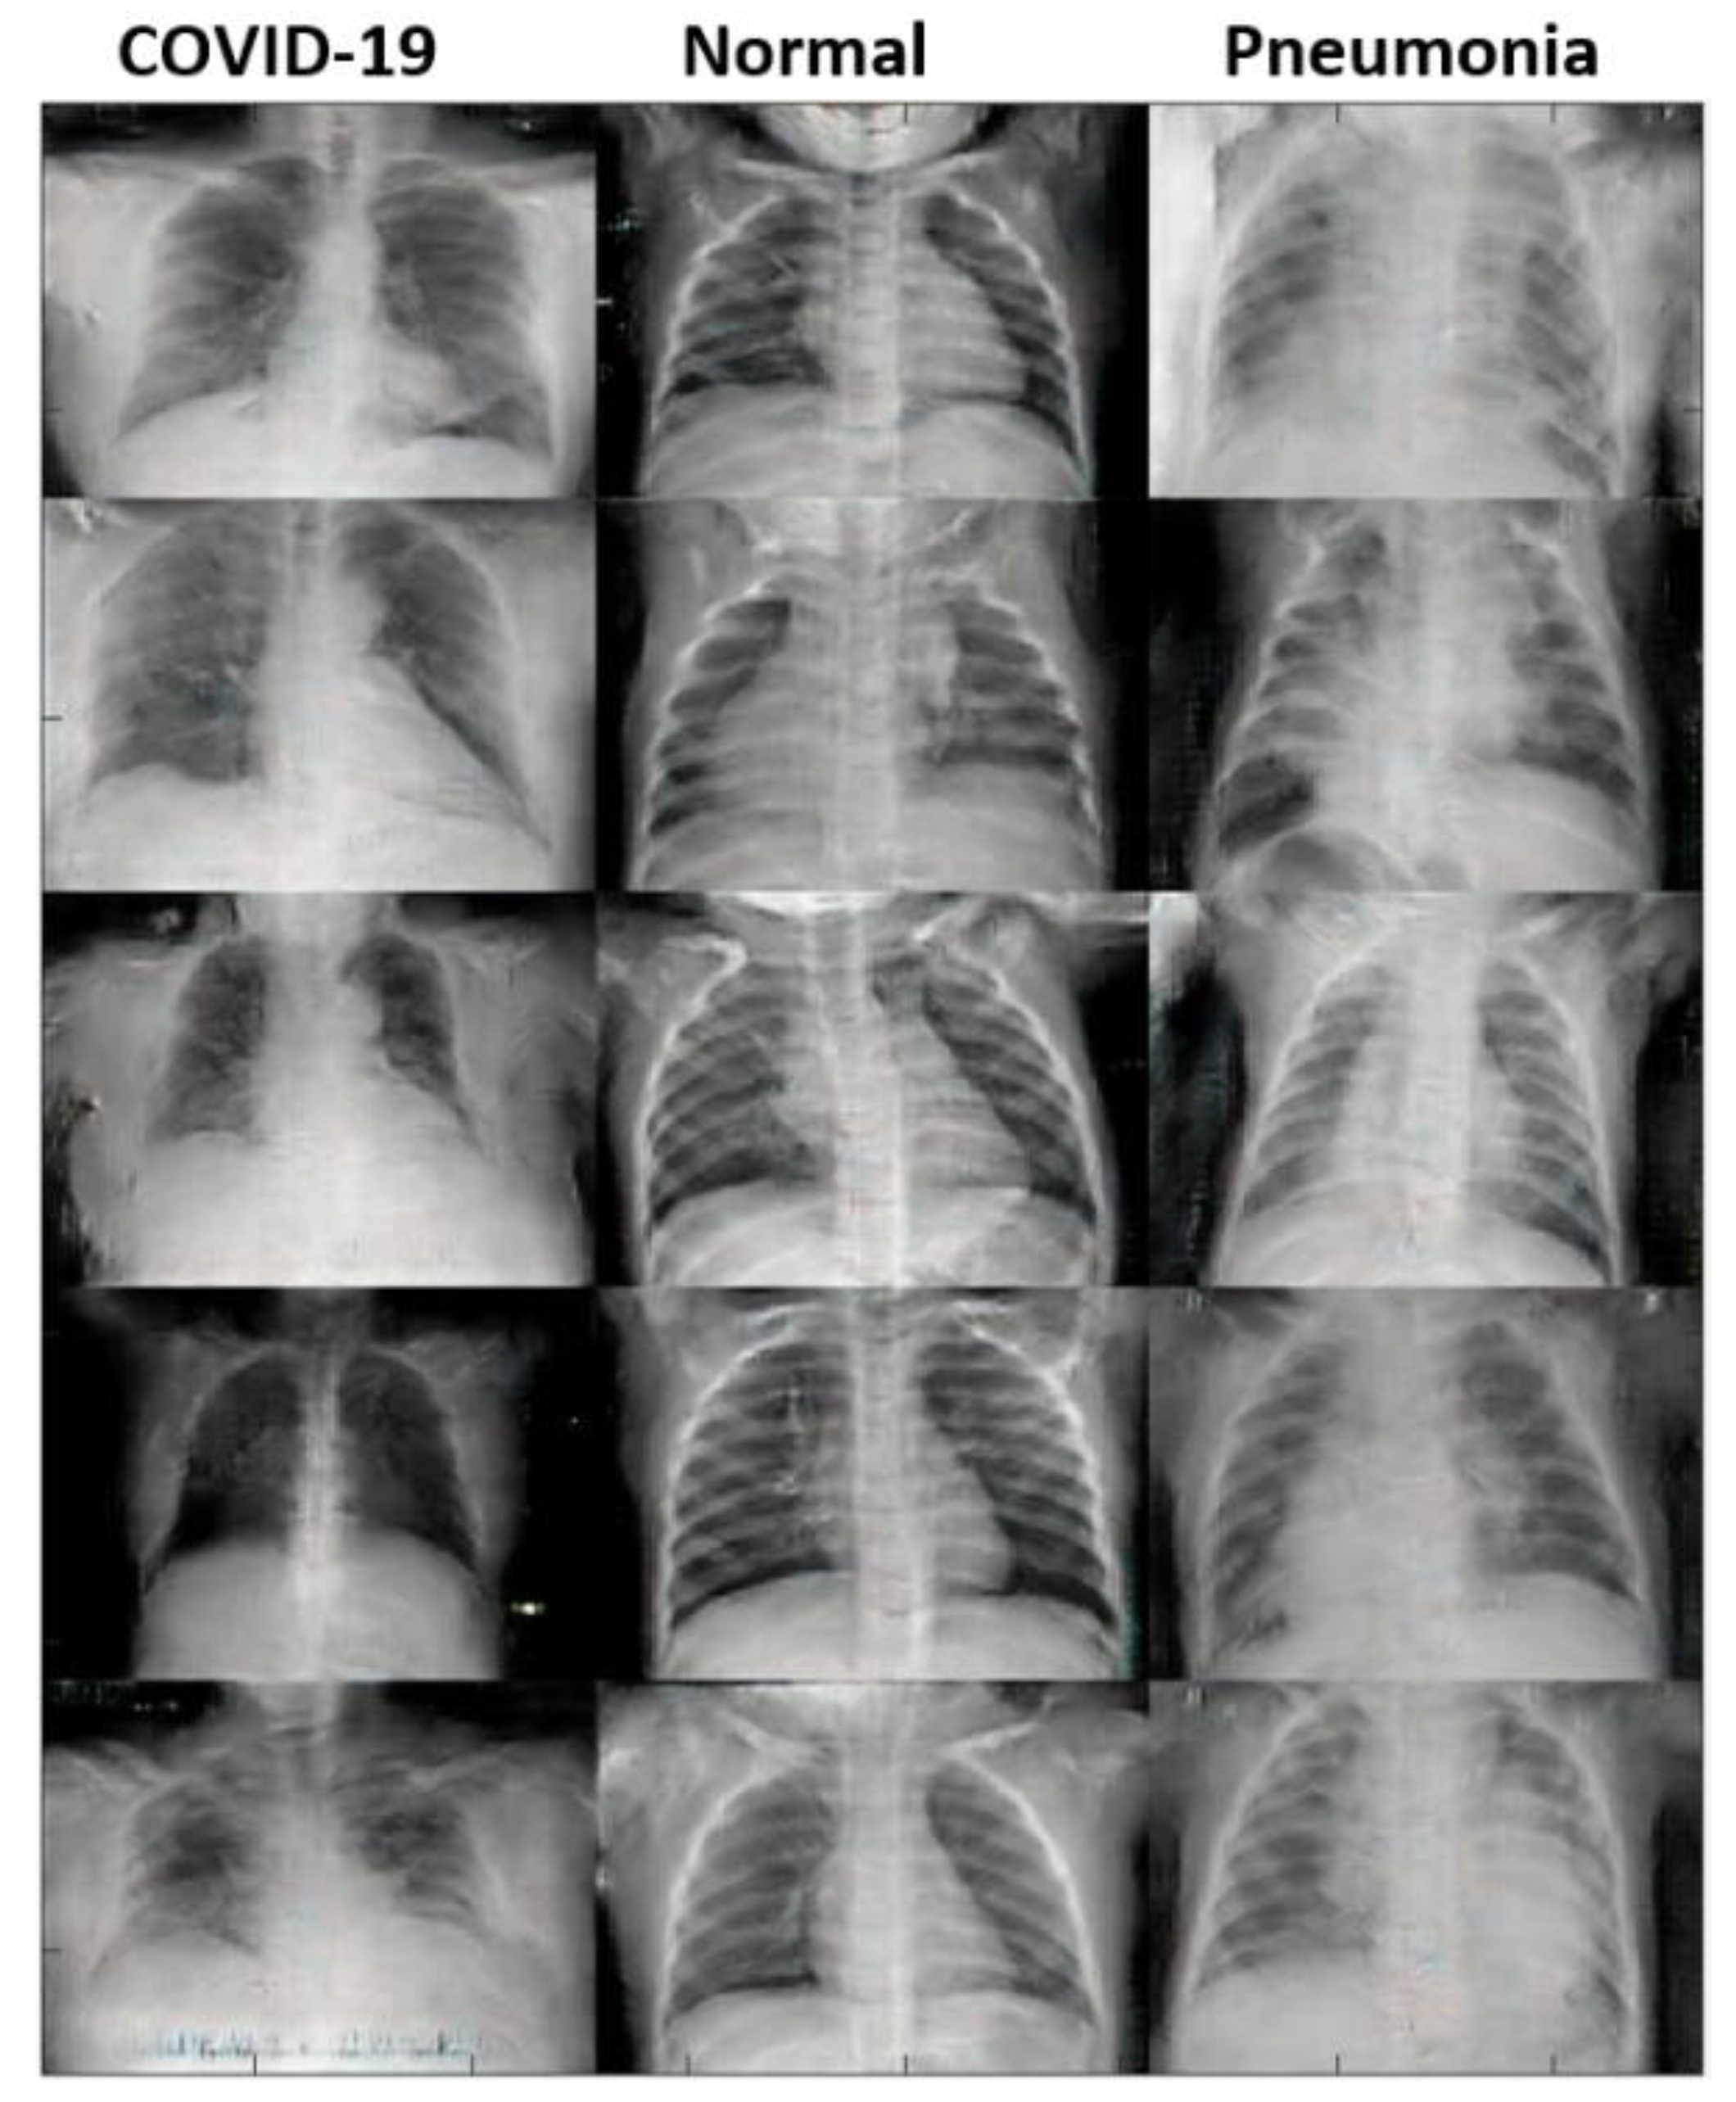

3.2.2. The Original Dataset